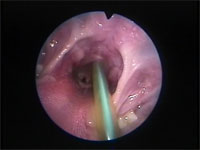

Abb 1 Kehlkopf-offen

Abbildung 1: Larynx der Katze. Rima glottidis (oben) und Plica vocalis sind geöffnet.

Der Larynx funktioniert wie eine Klappe zwischen den oberen und unteren Atemwegen. Seine wichtigsten Funktionen sind der Schutz der unteren Atemwege vor der Inhalation von Fremdkörpern, die Kontrolle des Atemwegdurchmessers während des Atmungszyklus und die Stimmbildung. Die Kehlkopftasche (Ventriculus laryngis) fehlt bei der Katze. Dorsal der Processi cuneiformes der beiden Aryknorpel befindet sich eine bei der Katze eine kleine schmal ovale Öffnung, die als Stimmritze (Rima glottidis) bezeichnet wird. Der Durchmesser der Stimmritze wird durch die Lage und Länge der Stimmfalten bestimmt, die wiederum von der Lage der Aryknorpel abhängen. Eine dorsolaterale Bewegung der Aryknorpel zieht die Stimmfalten auseinander und sorgt damit für eine Erweiterung der Stimmritze. Eine mediane Bewegung führt zu einer Verengung der Stimmritze bis auf eine schlitzartige Öffnung oder zu deren vollständigem Verschluss.